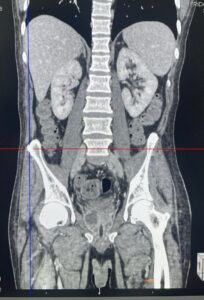

Realizou os exames de imagem abaixo: